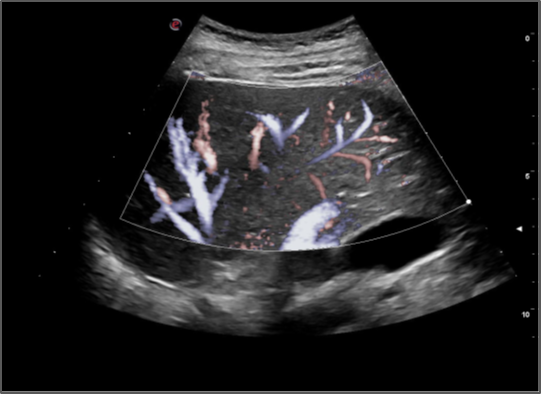

Phát hiện các mạch máu nhỏ nhạy hơn với công nghệ X-flow